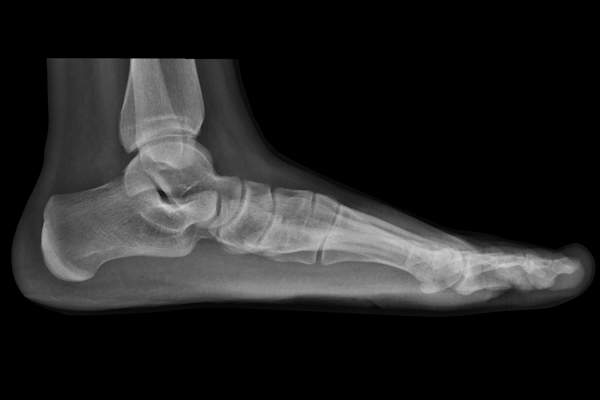

女性在五六十岁时平均每年增重1.5磅。即使是一点点的额外重量也会影响你脚上的足弓,因为在上面的额外重量等于在下面增加的压力。足弓会变弱,开始变平,甚至倒塌。具体来说,支撑足弓的肌腱,也就是胫骨后肌腱,会拉伤或撕裂。这种疼痛不适的专业术语是:足底筋膜炎。

也许这听起来像是太多伟哥的副作用,但僵拇实际上是大脚趾关节关节炎。症状包括在该加入大脚趾脚(疼痛加剧,你走一步,推动关闭)关节疼痛;在关节的灵活性损失;和炎症。你可以感谢父亲时间这个星座的症状,麻烦往往年龄30至60岁开始,随着时间的磨损导致脚的保护软骨打破,虽然遗传和先天畸形可以加速这一进程。

保守治疗包括冰,休息,矫形,和非处方消炎药。如果发现的足够早(在被称为拇外翻的阶段),一种被称为cheilectomy的手术可以改善运动,减轻疼痛,挽救关节。然而,等待太久,严重的关节炎就会发生。(多长时间太长因人而异,可根据x光片和症状确定。)如果发生这种情况,你可能最终需要更换关节或融合关节,这几乎总是提供缓解,但也意味着你将永远无法弯曲你的脚趾在那个关节。